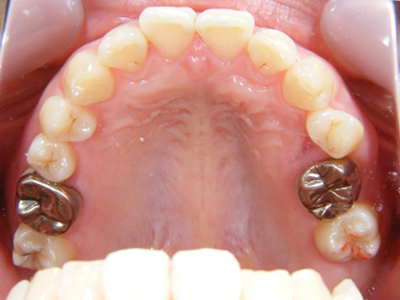

6. 施術前上顎観

上顎左右の8番(移植歯としての利用は断念)、および左上4番の抜歯した後の上顎写真です。これを見て思うのは、1歯レベルではとても良質の歯をしているのに、6番(6歳臼歯)が失活(神経を取った)又はかぶせ物がなされていることから、小学校から高校くらいまでの間は混合歯列期(乳歯と永久歯が共存している時期)や最初に萌出する6番の時期に、歯科的なアプローチが結果的に不十分だったことです。